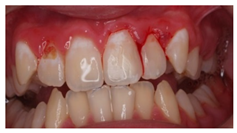

| 5 | In the image, various carious lesions in different evolutive states are presented 15 year-old patient. | ![]() | Which treatment alternatives would you select for this case? Select, individually, the treatment for teeth 1.3, 1.2, 1.1, 2.1, 2.2 y 2.3 from the given answers. |

| [11,13,14,32] | |